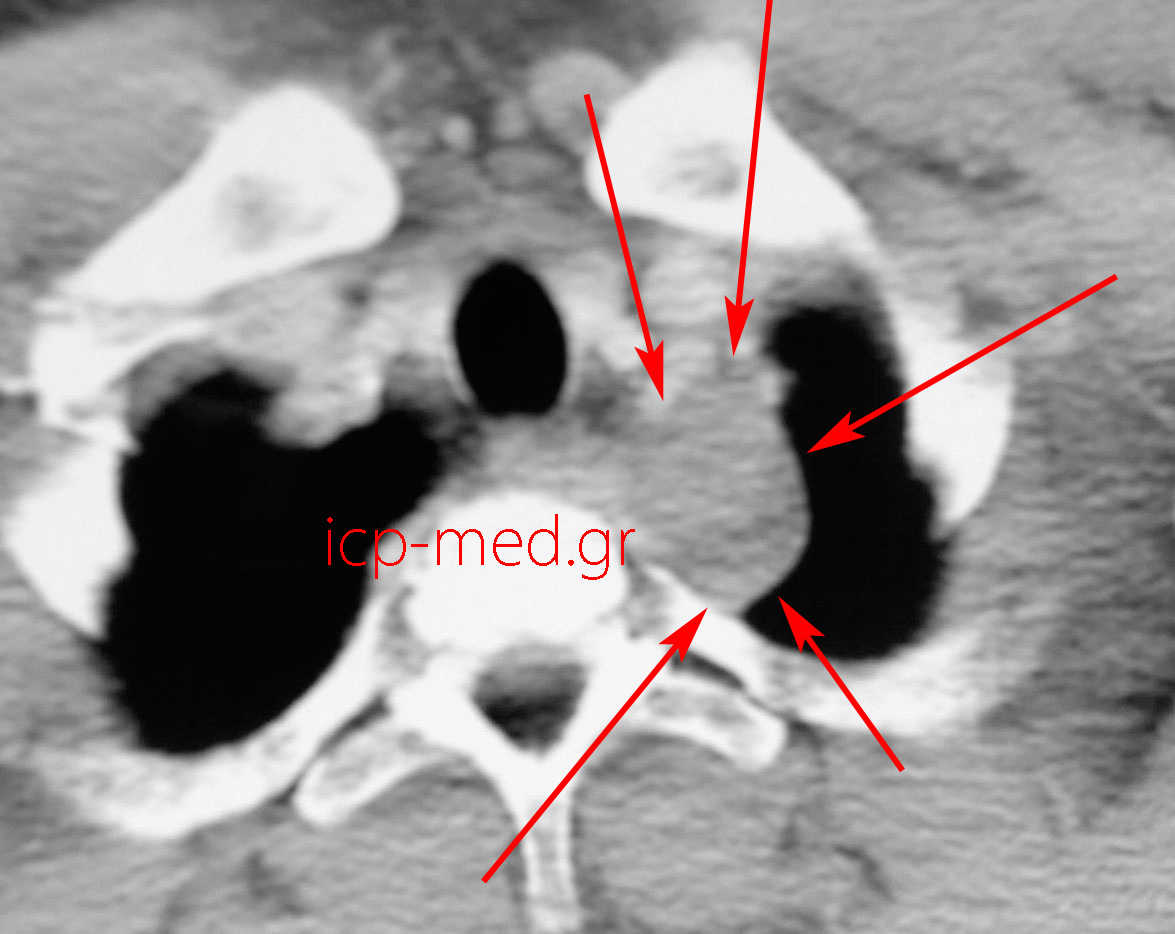

10.Preop CT (neuroganglioma)